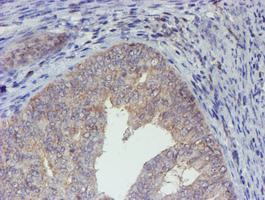

- IHC of paraffin-embedded Adenocarcinoma of Human endometrium tissue using anti-ELK3 mouse monoclonal antibody. (Heat-induced epitope retrieval by 10mM citric buffer, pH6.0, 100C for 10min).